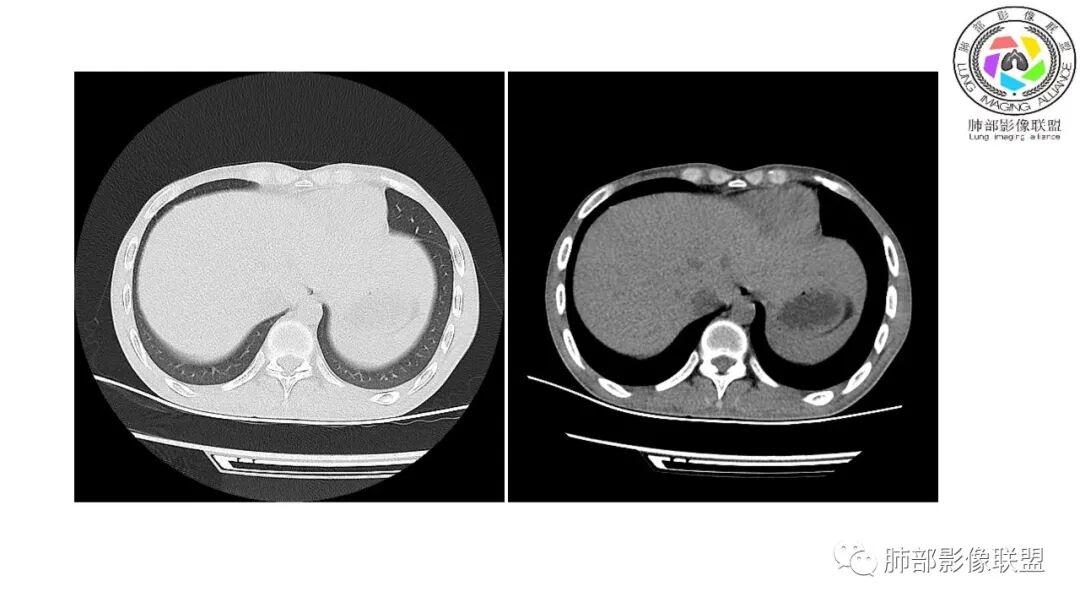

以下为2021-7-15日上腹部CT

影像与临床:1.青年男性,HlV阳性,颜面部皮疹(未提供皮疹图像)、发热(高热),实验室CRP、PCT高,T-Spot阴性。2.右肺下叶空洞结节,壁厚不均,边界清楚,其内线状影,未见液平及钙化,未见卫星灶,纵隔淋巴结增大,双侧腋窝见增大淋巴结。心腔内低密度提示贫血可能。肝脾影增大,未见结节影及块影。腹膜后见多发增大淋巴结。

综合分析:本例肺部影像学改变并不具有特征性,空洞性病灶须与多种疾病鉴别,但年轻HIV阳性患者,高热,皮疹,肝脾增大,纵隔、腋窝、腹膜后见多发增大淋巴结等都强烈提示马尔尼菲篮状菌感染的可能性。